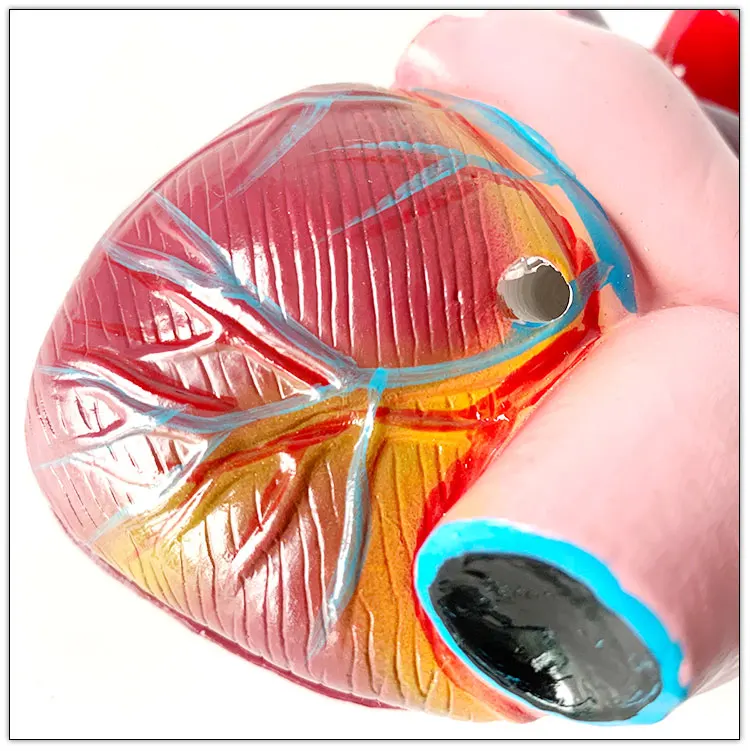

Valentine’s Day ช็อกโกแลตหัวใจ 12 ชิ้น – ของขวัญรังนกแท้ คอซซี่ โมเดลหัวใจมนุษย์ (Human Heart) | Shopee Thailand

โมเดลหัวใจมนุษย์ (Human Heart) | Shopee Thailand หัวใจมนุษย์ ภาพสต็อก – ดาวน์โหลดรูปภาพตอนนี้ – หัวใจ – อวัยวะภายใน …

ขยายกายวิภาคหัวใจมนุษย์รุ่น 3 ชิ้นส่วน – Buy กายวิภาคหัวใจ,หัวใจ … หัวใจมนุษย์ การออกแบบรายละเอียด ภาพประกอบสต็อก – ดาวน์โหลดรูปภาพตอนนี้ …

ชีวิตพลาสติกกายวิภาคหัวใจมนุษย์รุ่น2ชิ้นส่วน – Buy การสอนรุ่น,Anatomy … ช็อคโกแลตรูปหัวใจ [ภาพวาดฟรี] | OkusanPix

ชีวิตพลาสติกกายวิภาคหัวใจมนุษย์รุ่น2ชิ้นส่วน – Buy การสอนรุ่น,Anatomy … ขนมช็อกโกแลตแท่ง ตรา โชกี้ โชกี้ 1 บาท แพ็ค 100 ชิ้น | Shopee Thailand

ขนมช็อกโกแลตแท่ง ตรา โชกี้ โชกี้ 1 บาท แพ็ค 100 ชิ้น | Shopee Thailand ชีวิตพลาสติกกายวิภาคหัวใจมนุษย์รุ่น2ชิ้นส่วน – Buy การสอนรุ่น,Anatomy …

ชีวิตพลาสติกกายวิภาคหัวใจมนุษย์รุ่น2ชิ้นส่วน – Buy การสอนรุ่น,Anatomy … รักสุดใจ! ช่อช็อกโกแลตให้เธอ รวมไอเดียช่อช็อกโกแลตสื่อรัก มอบให้แฟน

In-306 3d กายวิภาคศาสตร์หัวใจมนุษย์รูปแบบทางการแพทย์พลาสติกกายวิภาค … หัวใจมนุษย์ ภาพสต็อก – ดาวน์โหลดรูปภาพตอนนี้ – หัวใจ – อวัยวะภายใน, การ …

หัวใจวิทยาศาสตร์เรื่องกายวิภาคศาสตร์ทางการแพทย์หัวใจมนุษย์รุ่นขาย – Buy … หัวใจวิทยาศาสตร์เรื่องกายวิภาคศาสตร์ทางการแพทย์หัวใจมนุษย์รุ่นขาย – Buy …

หัวใจวิทยาศาสตร์เรื่องกายวิภาคศาสตร์ทางการแพทย์หัวใจมนุษย์รุ่นขาย – Buy … Anatomy หัวใจมนุษย์รุ่นพลาสติกทางการแพทย์กายวิภาคหัวใจจัมโบ้รุ่นอวัยวะ …

Anatomy หัวใจมนุษย์รุ่นพลาสติกทางการแพทย์กายวิภาคหัวใจจัมโบ้รุ่นอวัยวะ … รูปช็อกโกแลตหัวใจพร้อมน้ำเชื่อม PNG , วาเลนไทน์วัน, หัวใจ, วันแห่งความ …

3d Anatomy หัวใจมนุษย์รุ่นพลาสติกทางการแพทย์กายวิภาคหัวใจจัมโบ้รุ่น … หัวใจวิทยาศาสตร์เรื่องกายวิภาคศาสตร์ทางการแพทย์หัวใจมนุษย์รุ่นขาย – Buy …

หัวใจวิทยาศาสตร์เรื่องกายวิภาคศาสตร์ทางการแพทย์หัวใจมนุษย์รุ่นขาย – Buy … ส่งไว🚀24ชม. เจบีช็อกโกแลต รูปฟุตบอล เหรียญทอง เหรียญเงิน ทองแท่ง หัวใจ …

Anatomy หัวใจมนุษย์รุ่นพลาสติกทางการแพทย์กายวิภาคหัวใจจัมโบ้รุ่นอวัยวะ … ภาพประกอบแบนเวกเตอร์หัวใจมนุษย์ขนาดใหญ่บนพื้นหลังสีขาว ภาพประกอบสต็อก …

หัวใจมนุษย์กายวิภาครุ่นวิทยาศาสตร์การแพทย์รูปแบบการสอน ห้องหัวใจมนุษย์: คำอธิบายโครงสร้างหน้าที่และประเภท

หุ่นจำลองหัวใจมนุษย์ 3d มนุษย์กายวิภาครุ่นหัวใจมนุษย์สำหรับซัพพลายเออร์แบบครบวงจรวิทยาศาสตร์ …

3d มนุษย์กายวิภาครุ่นหัวใจมนุษย์สำหรับซัพพลายเออร์แบบครบวงจรวิทยาศาสตร์ … 3d Anatomy หัวใจมนุษย์รุ่นพลาสติกทางการแพทย์กายวิภาคหัวใจจัมโบ้รุ่น …

3d Anatomy หัวใจมนุษย์รุ่นพลาสติกทางการแพทย์กายวิภาคหัวใจจัมโบ้รุ่น … อวัยวะหัวใจของมนุษย์ | องค์ประกอบกราฟฟิก แบบ PSD ดาวน์โหลดฟรี – Pikbest

หัวใจมนุษย์กายวิภาครุ่นวิทยาศาสตร์การแพทย์รูปแบบการสอน 15 Porch ช็อกโกแลต Fudge แม่พิมพ์ซิลิโคนหัวใจรูปเค้กช็อกโกแลตตกแต่ง DIY …

อุปกรณ์การศึกษากายวิภาคศาสตร์รุ่นหัวใจมนุษย์รุ่นสำหรับโรงเรียนขนาดชีวิต … วิธีทำ “นามะช็อกโกแลต” ของฝากยอดฮิตจากญี่ปุ่น อร่อยหรูดูแพง แต่ทำง่าย …

In-306 3d กายวิภาคศาสตร์หัวใจมนุษย์รูปแบบทางการแพทย์พลาสติกกายวิภาค … บอลลูนหัวใจมนุษย์ Angioplasty เวกเตอร์ ภาพประกอบ ภาพประกอบสต็อก – ดาวน์ …

โรงงานโดยตรงขาย Anatomy หัวใจมนุษย์การฝึกอบรมชุดอวัยวะภายในรุ่น – Buy …